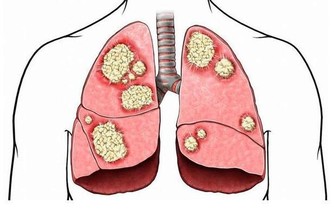

想要胃好好的,除了要改掉上述的惡習,還要及時發現胃的“委屈”,緩解胃的“傷害”,否則等到胃癌來敲門,就晚了。

如果你經常出現下面幾種情況,最好考慮做一下胃鏡檢查。